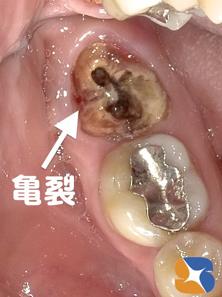

奥歯が真ん中で2分割 ヒビ 銀歯を外して見ると、虫歯が根にまで進行してもろもろ崩壊状態。更に奥歯の中央には亀裂(マイクロスコープでチェック)を確認。この状態なら抜歯を宣告されても無理はないと思われました。

しかし、鈴木歯科では、大臼歯を2分割して、崩壊の激しい奥側を抜いて、何とか保存できそうな手前側の根を残すことに決まりました。